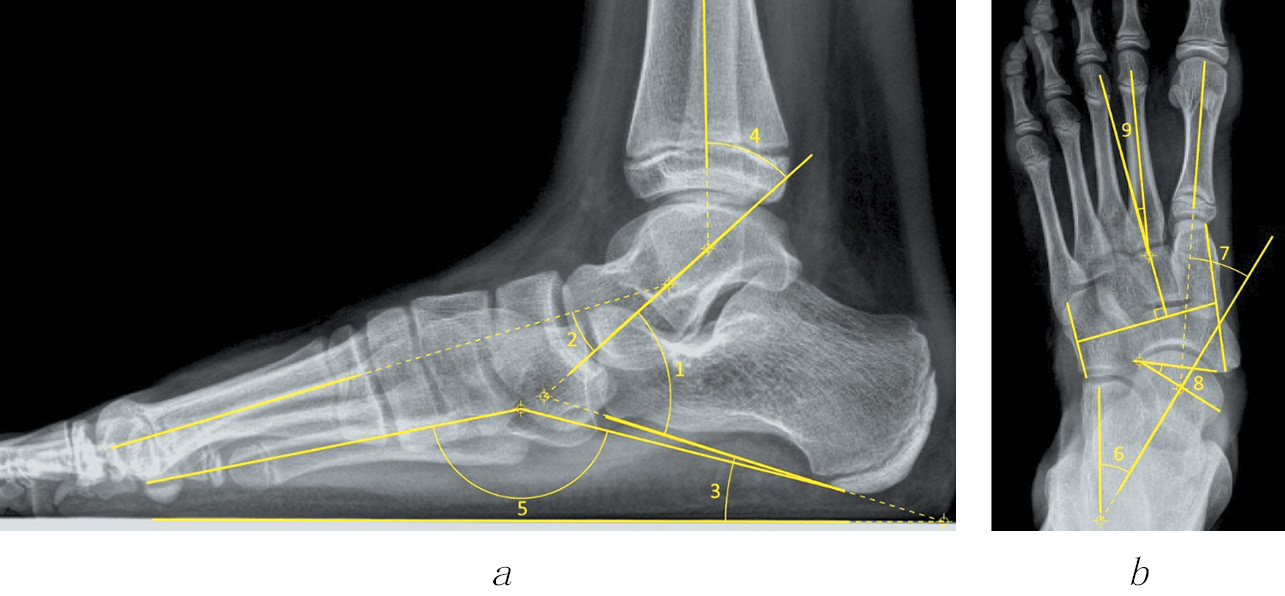

Как видно из табл. 1, углы, используемые в исследовании, характеризовали степень деформации как в сагиттальной, так и во фронтальной плоскости. Методика измерения указанных углов приведена на рис. 2.

Рис. 2. Схема построения углов на рентгенограмме стопы в боковой (а) и переднезадней (б) проекциях (пояснения см. в тексте)

Построение углов на боковой и переднезадней рентгенограммах стопы осуществляли в соответствии с общепринятыми правилами, как изображено на рис. 2. При этом угол Kite (1) на боковой рентгенограмме образован линией оси таранной кости и линией, проведенной по нижним точкам пяточного бугра и переднего отростка пяточной кости. Угол Meary (2) образован линиями осей таранной и I плюсневой кости. Угол наклона пяточной кости (3) — это угол между линией опорной поверхности и нижними точками пяточного бугра и переднего отростка пяточной кости. Таранно-большеберцовый угол (4) образован пересечением оси таранной и большеберцовой кости. Угол продольного свода (5) построен по методике Ф.Р. Богданова и расположен между нижней точкой ладьевидно-клиновидного сустава, а также нижними точками I плюсневой и пяточной кости. Угол Kite (6) на переднезадней рентгенограмме образован пересечением линий осей таранной и пяточной кости. Угол Meary (7) так же, как и на боковой рентгенограмме, определяют при пересечении оси I плюсневой и таранной кости. Угол латерального смещения ладьевидной кости (8) строили по крайним точкам суставных поверхностей таранной и ладьевидной кости в таранно-ладьевидном суставе. Угол приведения переднего отдела стопы (9) был образован линией оси II плюсневой кости и перпендикуляром, восстановленным из середины линий по медиальной и латеральной границам среднего отдела стопы.